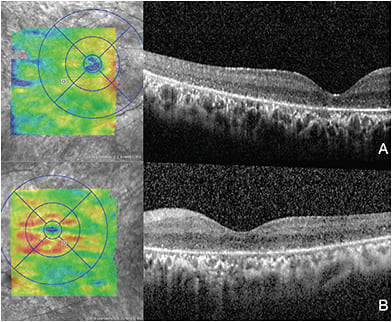

Examination of the posterior segment revealed diffuse and significant retinal atrophy involving the entire periphery and macula in the right eye. There were nearly identical findings in the left eye, not significantly sparing parts of the fovea. The retinal vasculature was severely attenuated in both retinas; there were bone spicules present and mild optic nerve pallor OU (Figures 1 and 2). Optical coherence tomography (OCT) testing revealed that the inner and outer segments were largely attenuated OU (Figure 3).